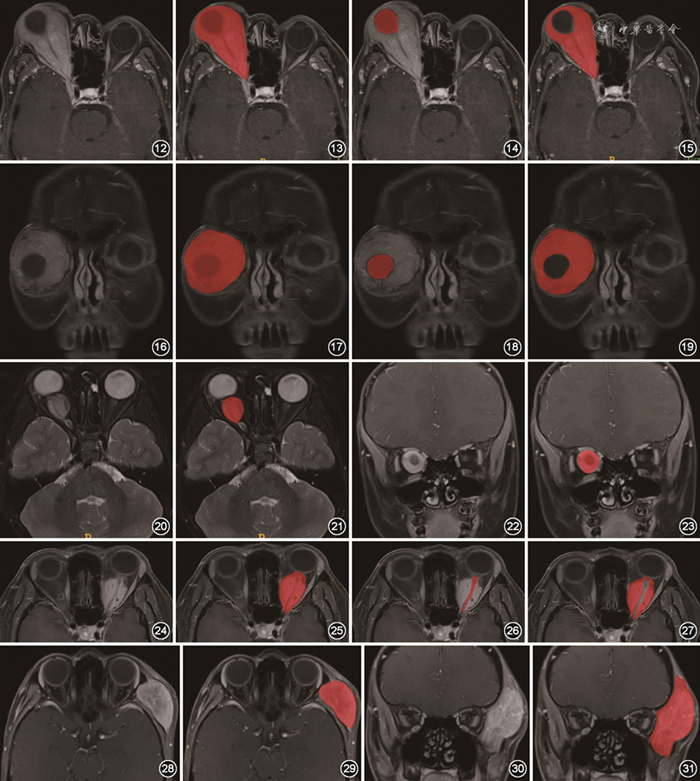

(3)包绕眼球的肿块。当肿块包绕眼球不超过1/2眼周时,采用直接勾画的方式完成标注;当肿块生长超过1/2眼周时,勾画时要特别注意“首尾重叠”,避免遗漏病变;当肿块完全包绕眼球时,结合横断面T2WI及增强T1WI图像进行标注,首先标注肿块整体和眼球,然后单独标注眼球,前者减去后者即为肿块,勾画示意图见图12~19。

图12~19 眼眶肿块完全包绕眼球的勾画示意图。病理证实为淋巴瘤,肿块完全包绕眼球。首先标注肿块整体和眼球(图12,13),再单独标注眼球(图14),两者减影后获得标注肿块的图像(图15)。图16~19为相应冠状面图像

图20~23 视神经肿块标注示意图。病理结果为视神经胶质瘤,联合T2WI(图20,21)和增强T1WI(图22,23),沿病变显示最大轮廓标注,图21,23为标注后图像

图24~27 视神经鞘肿块标注示意图。病理结果为视神经鞘脑膜瘤,首先标注肿块整体和视神经(图24,25),然后标注未强化的视神经(图26),两者减影即为标注的视神经鞘肿块(图27)

图28~31 眶壁及骨膜下间隙肿块标注示意图。病理为横纹肌肉瘤,结合平扫T1WI(图28,29)和脂肪抑制增强T1WI(图30,31),对整个肿块进行标注,图29,31为标注后图像

(4)视神经及视神经鞘肿块。①视神经肿块,联合T2WI和增强T1WI图像,沿病变显示最大轮廓标注,勾画示意图见图20~23。②视神经鞘肿块,在横断面脂肪抑制增强T1WI图像标注,首先标注肿块整体和视神经,然后标注未强化的视神经,前者减去后者即为视神经鞘肿块,勾画示意图见图24~27。③视神经及视神经鞘肿块累及颅内时,同时标注颅内病变。

(5)眶壁及眶骨膜下肿块。结合平扫T1WI和脂肪抑制增强T1WI,对整个肿块进行标注,勾画示意图见图28~31。